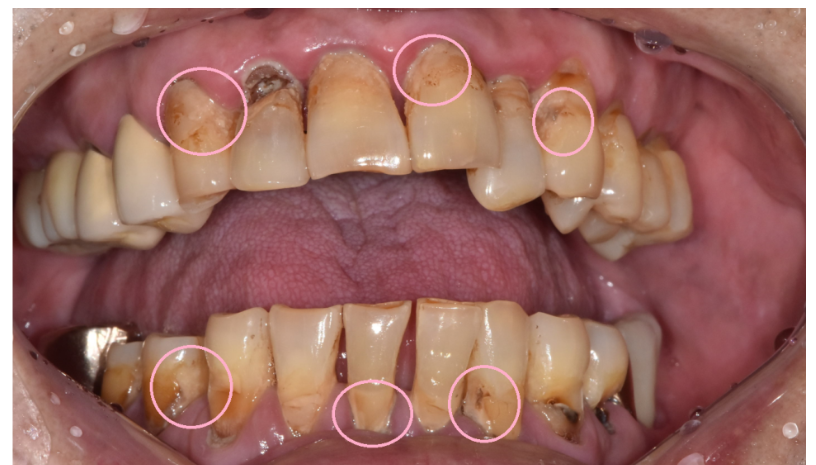

또한 수술 당일에는 양치를 하고 방문해주세요.

입안을 깨끗이 유지되는 것이

감염 위험을 크게 낮출 수 있습니다.

이런 이유로 수술 전 스케일링을 하기도 하고요.

240425 입안에 찌꺼기가 끼면 감염 위험성이 높아집니다.